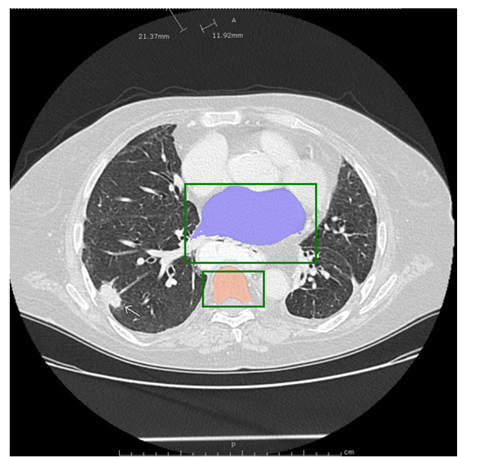

医学图像:

该图片是测试图片,从网站上下载的。